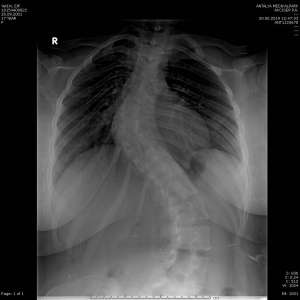

Skolyoz, omurganın göğüs veya bel bölgelerinde görülebilen, yana doğru eğriliğidir. Normal ve sağlıklı omurgada omurlar arkadan bakıldığında yukardan aşağıya yani boyun, sırt ve bel bölgelerinde düz bir hat şeklinde uzanır.

Skolyozda ise omurlar sağa veya sola doğru yer değiştirir ve aynı zamanda kendi eksenleri etrafında döner. Omurgaya arkadan bakıldığında eğrilik düz durulduğunda bile fark edilebildiği gibi bazen bu denli net değildir ve ancak öne eğilme durumunda, kontroller ve röntgen filmlerinde anlaşılabilir.

Skolyoz tanısı ayakta çekilen tüm omurgayı içine alan röntgen filmi ve klinik muayenede yukarıda sayılan belirtilerin bir veya birkaçının bulunması ile konulur. Skolyoz tanısı konulduğunda sebebe yönelik MR incelemesi gereklidir.

Ayakta çekilen tüm omurganın ön arka ve yan radyografilerinde, eğriliğin başladığı ve sonlandığı omurlar arasındaki açı ölçülür ve bu açının ilerlemesine göre takip edilir. Bu açıya Cobb açısı denir.

Skolyoz Görselleri